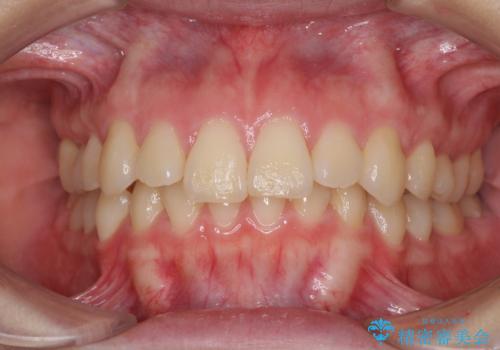

前歯の捻れを改善 インビザラインによる矯正治療